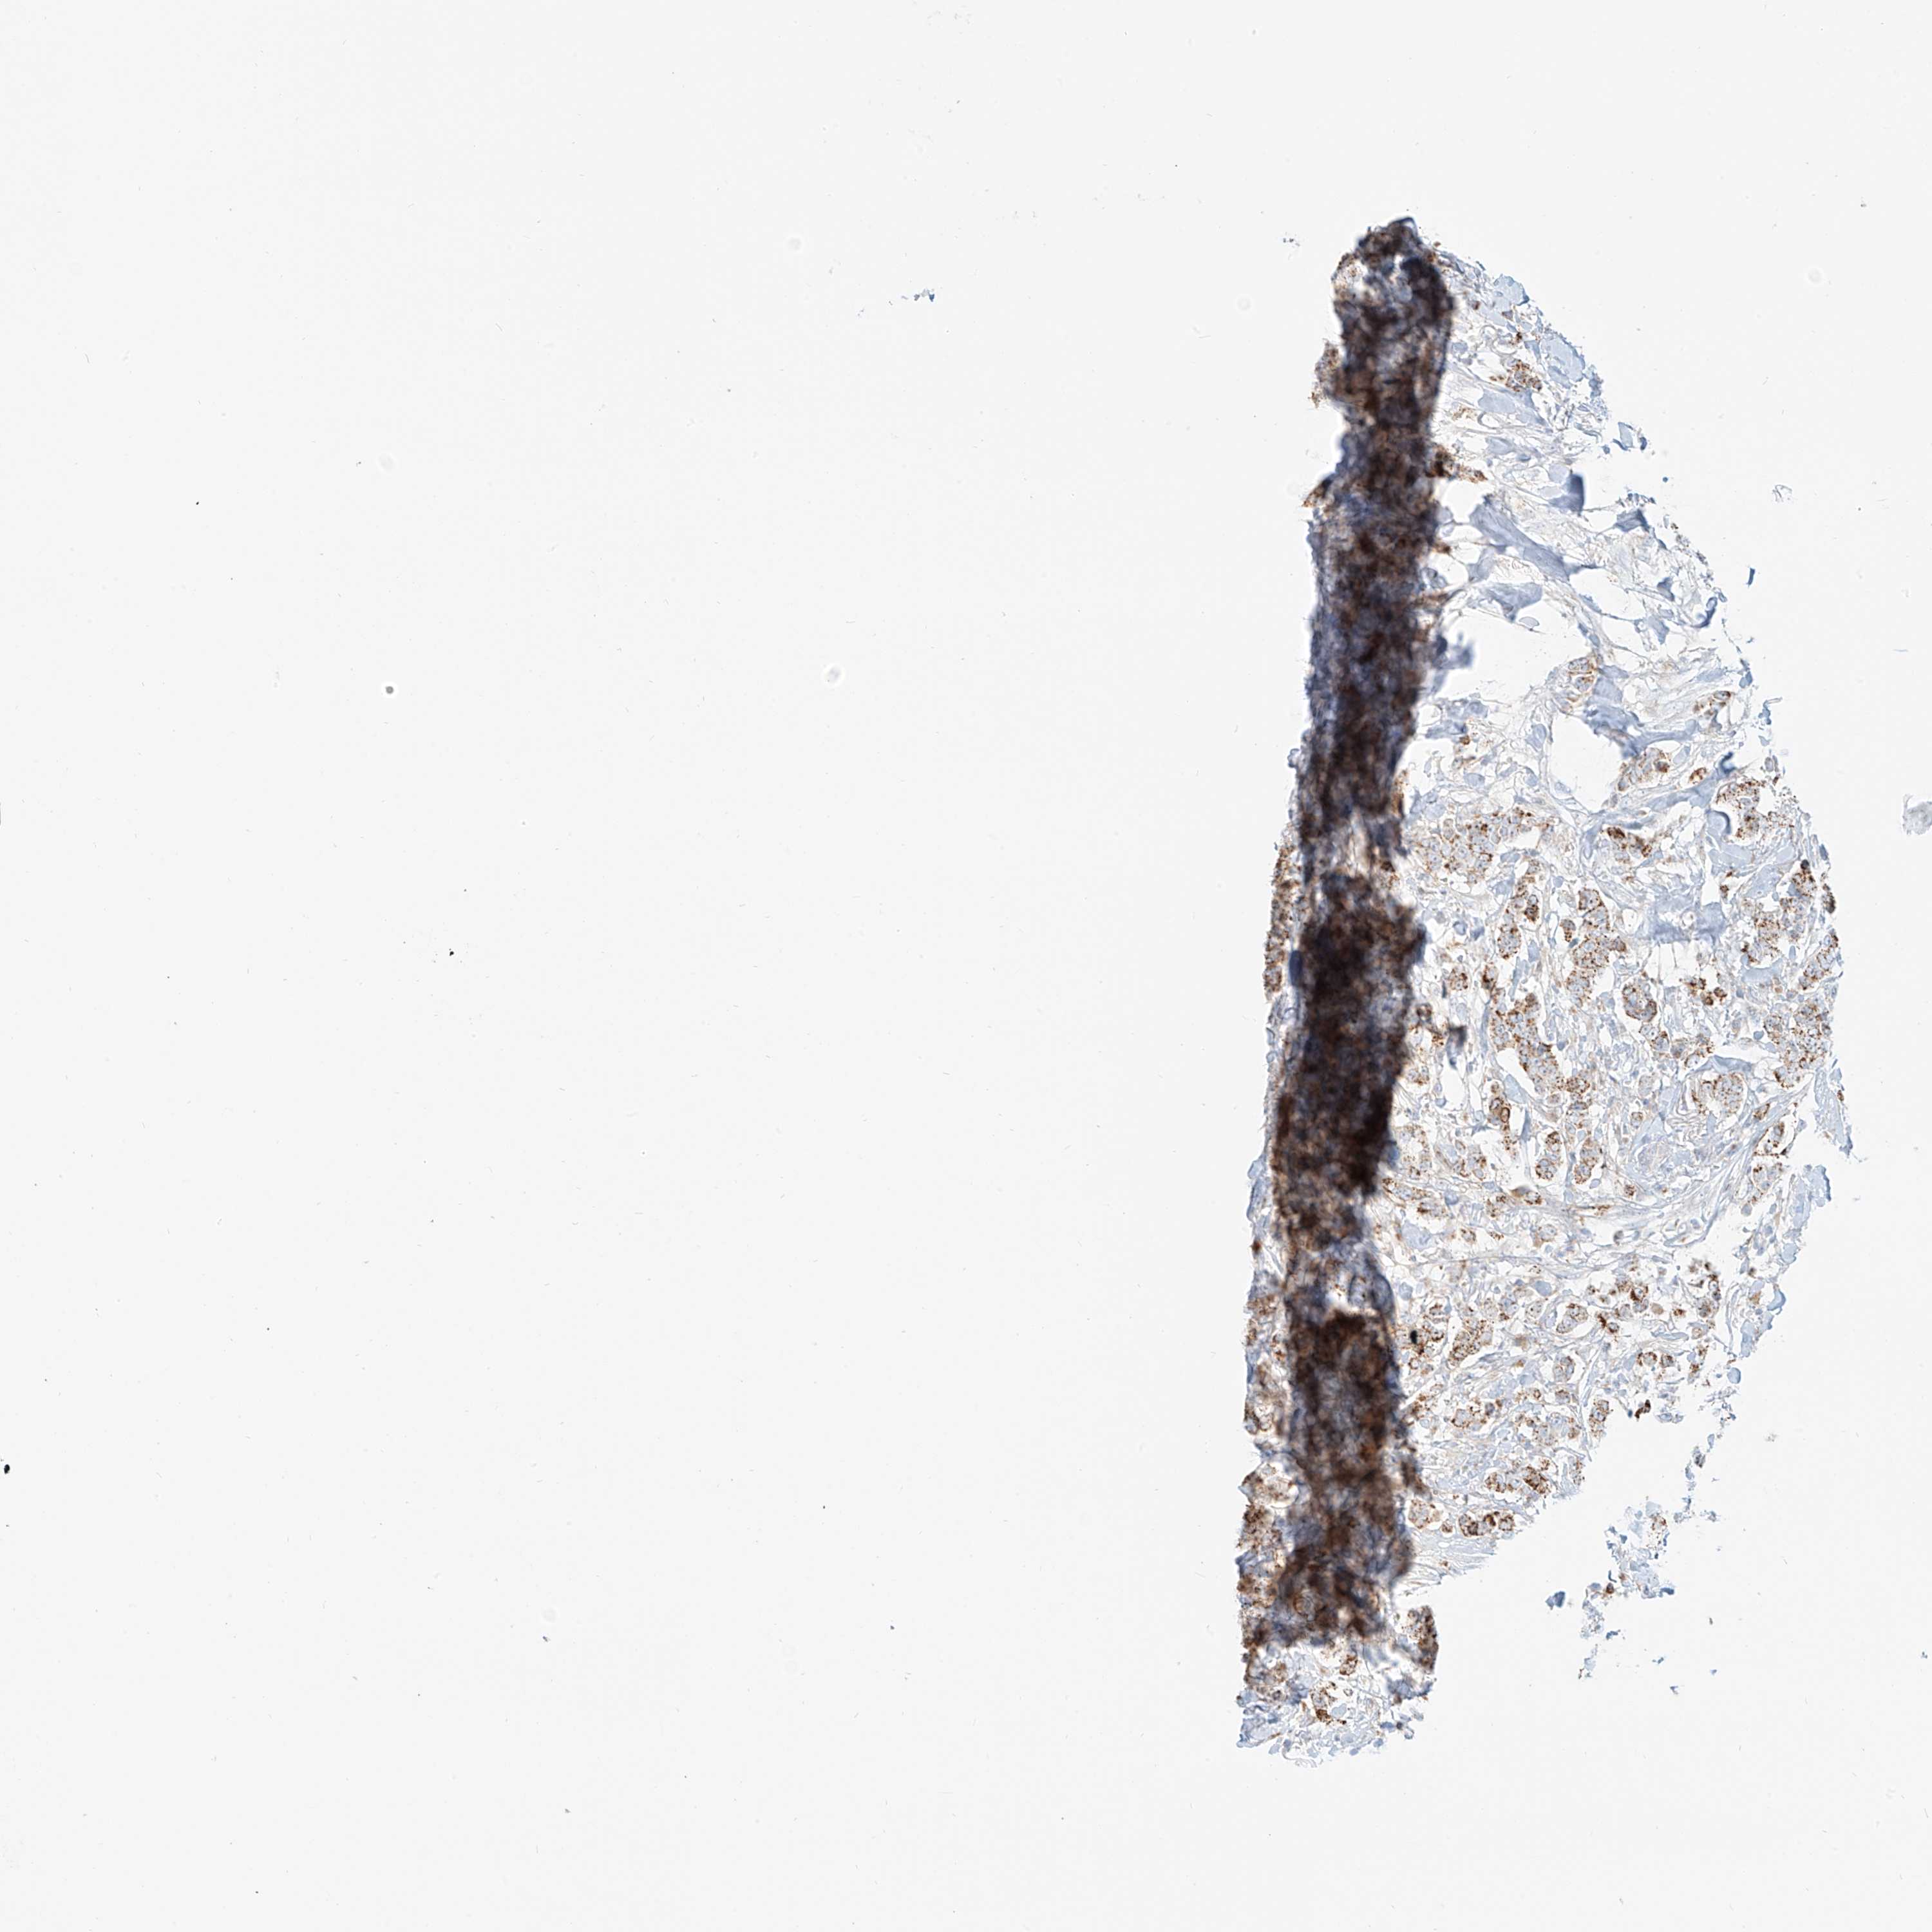

BRCA TCGA BRCA VALIDATION PROTEIN EXPRESSION